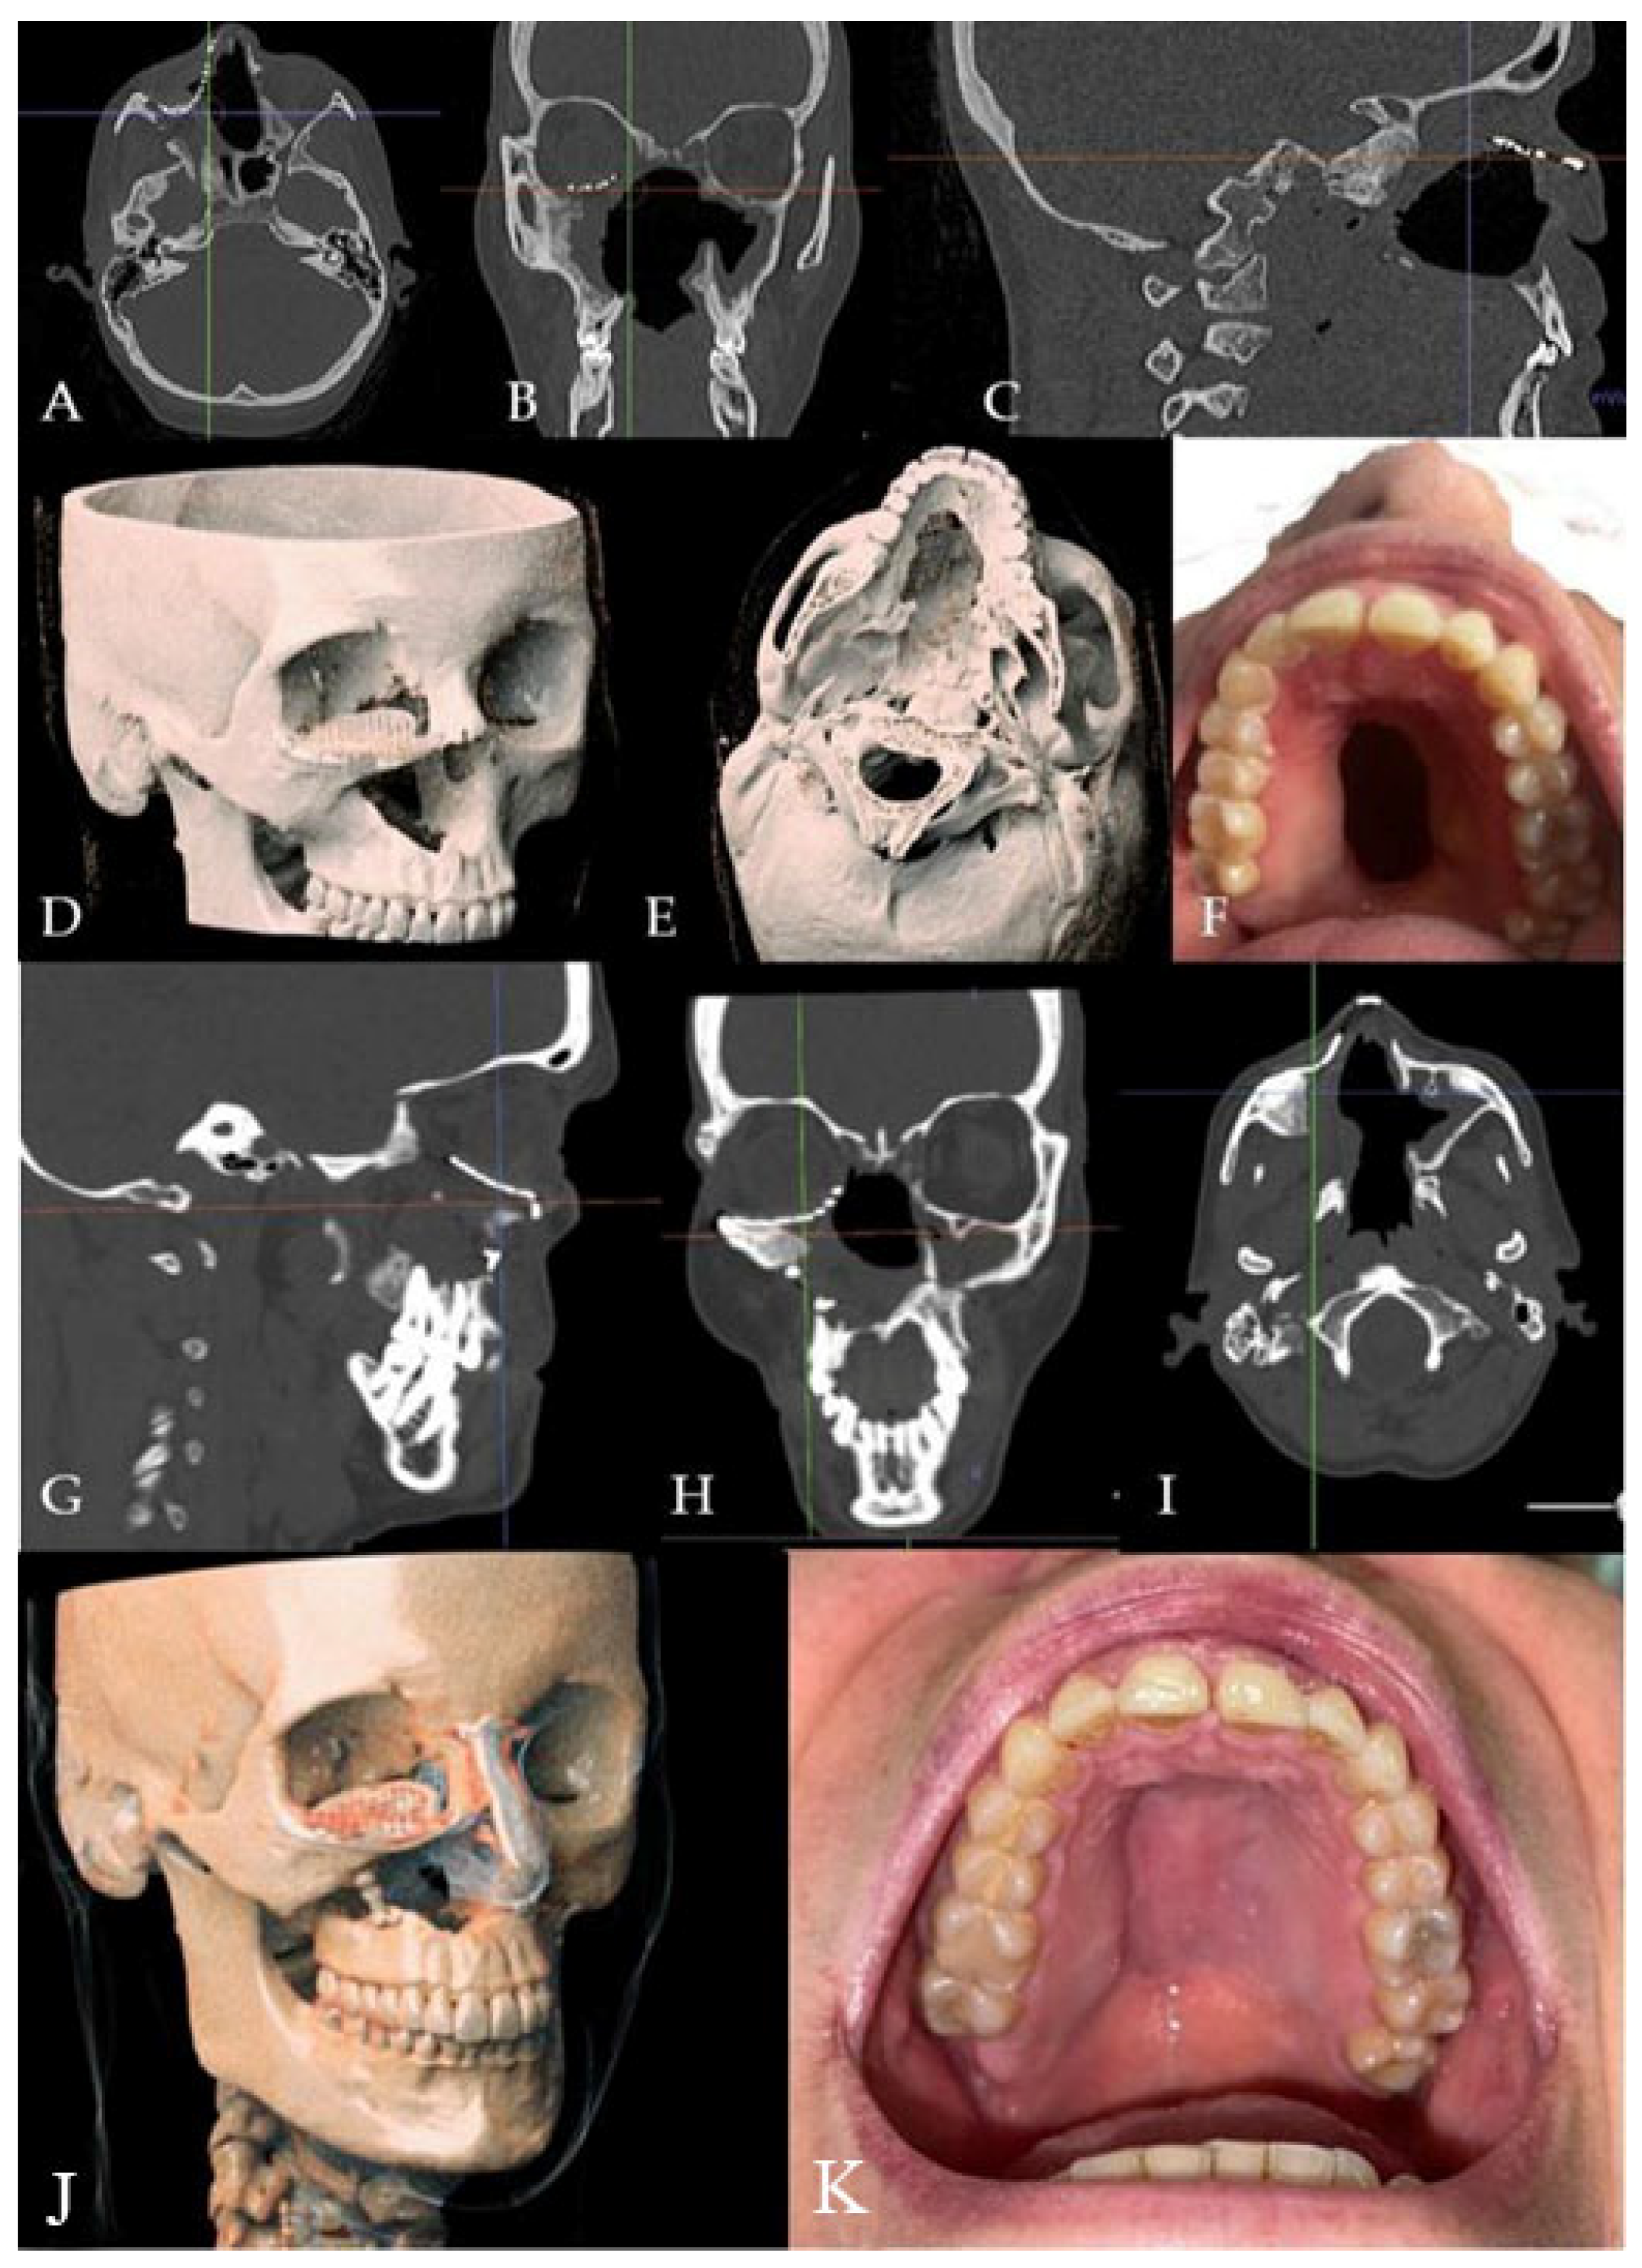

A 52-year-old male patient came to our attention in 2017, presenting with a palatal/oro-nasal fistula measuring 3.5 cm in diameter along the major axis, with atrophic soft tissues surrounding the lesion (Ia according to the Okay et al. classification [14]). The patient had already been treated in 2015 in another center using a palatal local flap with no success and was then treated with an obturator. At the clinical and radiographic examination (Figure 4), a wide oro-nasal communication with exposure of the nasal cavity and septum was observed, leading to speech disturbances, rhinolalia, and eating difficulties.

Figure 4. (A) Clinical presentation of the oro-nasal communication. In inset A, it is possible to appreciate the visibility of the nasal septum. (B,C) Radiographic and 3D reconstruction using InVivo6® and Anatomage Table EDU vers.8® (Santa Clara, CA, USA) software. DICOM files were imported in InVivo6® (Santa Clara, CA, USA) software to obtain the axial, cross, and panorex sections. Afterwards, the DICOM files were imported into Anatomage Table EDU vers.8® (Santa Clara, CA, USA) to obtain the 3D rendering.

In 2018, after 4 years of sobriety, the patient underwent surgical intervention for palate reconstruction. The Le Fort I osteotomy was preceded by preplating to achieve the correct repositioning of the fragment (Figure 5). A careful dissection of the nasal and palatal mucosa was performed after the down fracture. A temporalis muscle rotation flap was harvested on the right side. The operation lasted three hours in the oro-tracheal tube. A nasogastric tube was placed and kept in place for seven days with standard antibiotic and anti-inflammatory therapy. The patient was discharged after four days.

Figure 5. The surgery was performed, using a Le Fort I osteotomy preceded by preplating to achieve the correct repositioning of the fragment; a careful dissection of the nasal and palatal mucosa was performed after the down fracture.

The patient attended follow-up appointments at 1 week, 1 month, 6 months, and one year, with complete resolution of the fistula. The patient showed an improved ability to speak and no issues with eating, as confirmed by clinical and radiographic controls (Figure 6).

Figure 6. (A) One-year clinical follow-up. (B) Radiological one-year follow-up.

The patient attended follow-up appointments at 1 week, 1 month, 6 months, and 1 year, with complete resolution of the fistula, improved speech capacity, and no difficulties with eating (Figure 7).

Figure 7. (AE) Radiographic and 3D reconstruction using InVivo6® and Anatomage Table EDU vers.8® (Santa Clara, CA, USA) software. DICOM files were imported in InVivo® (California, USA) software to obtain the axial, cross, and panorex sections. Afterwards, the DICOM files were imported into Anatomage Table® (Santa Clara, CA, USA) to obtain the 3D rendering. (F) Clinical presentation of the oro-nasal communication. (GJ) Radiographic and 3D reconstructions using InVivo6® and Anatomage Table EDU vers.8® (Santa Clara, CA, USA) software at the one-year follow-up. (K) One-year clinical follow-up.